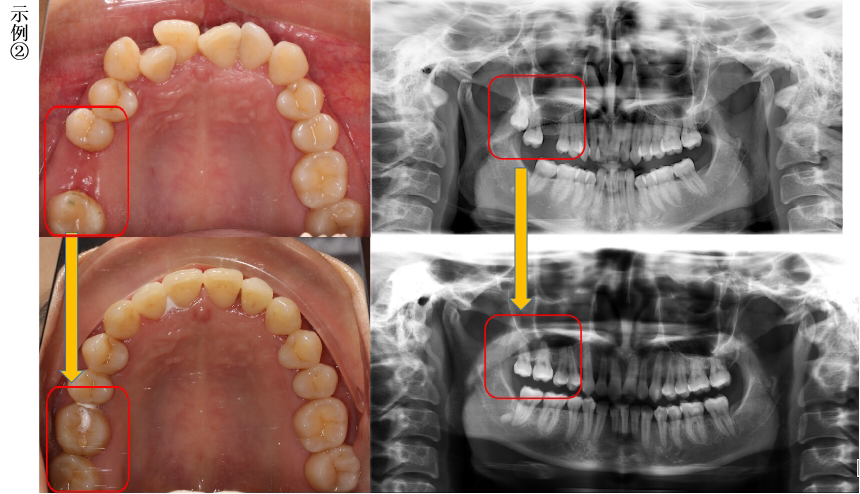

磨牙龋坏,智齿成功替代

磨牙缺失,智齿成功替代

磨牙烂根,智齿成功替代